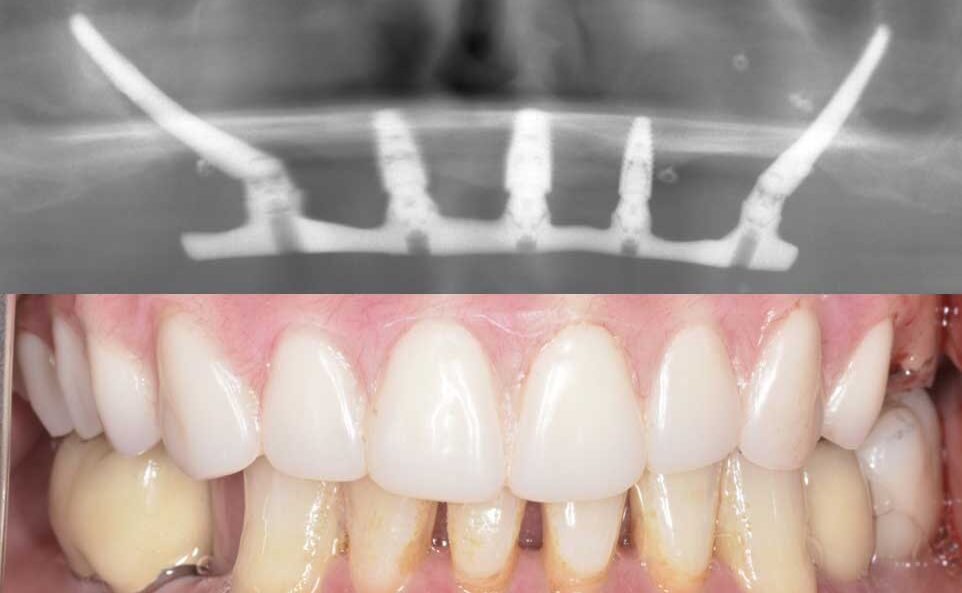

治療前

インプラント治療 オールオン4

治療後

虫歯と歯周病でボロボロになった歯の抜歯を行い、当日に4本のインプラントを埋入し,仮歯まで装着しました。